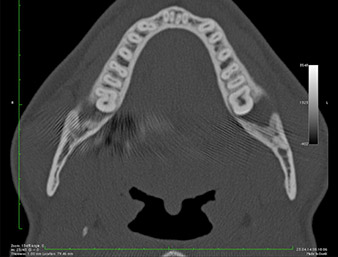

It could be seen in the 3D image (digital volume tomography) that the root remnant was located disto-caudally in the transition from the horizontal to the ascending portion of the mandible (Fig. 2).